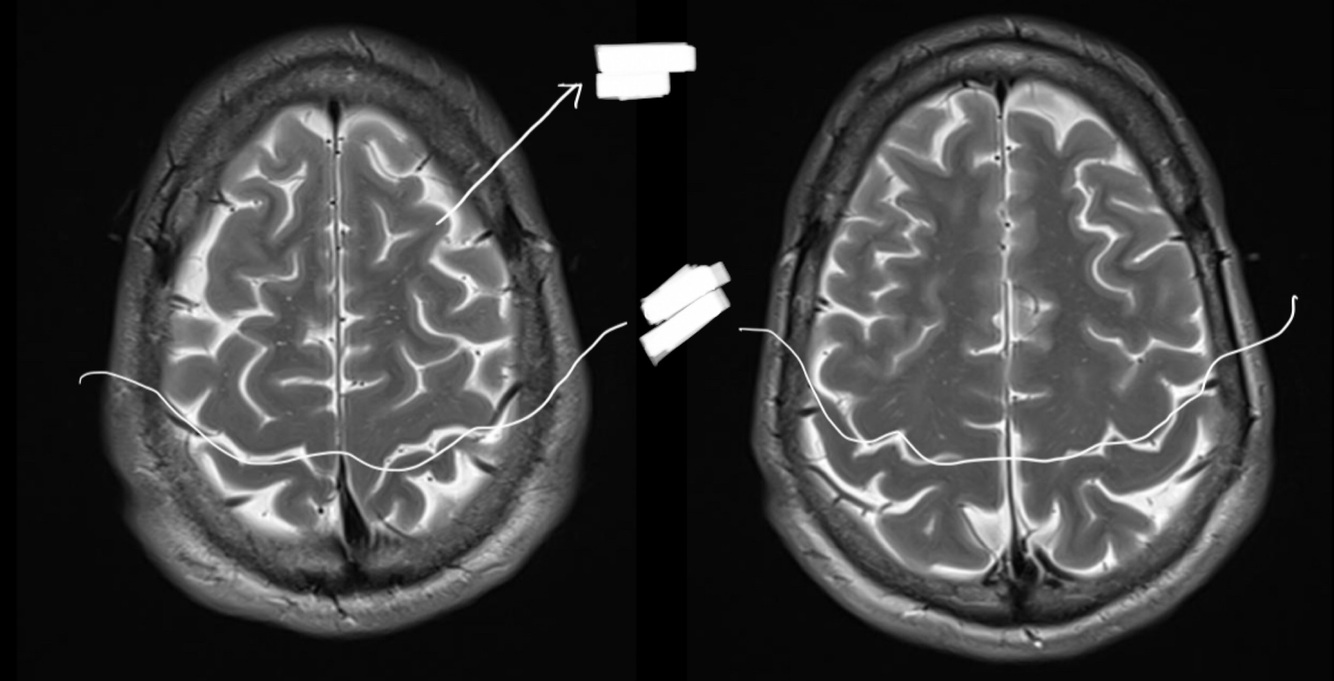

In this image we can see the…

Sylvian sulcus